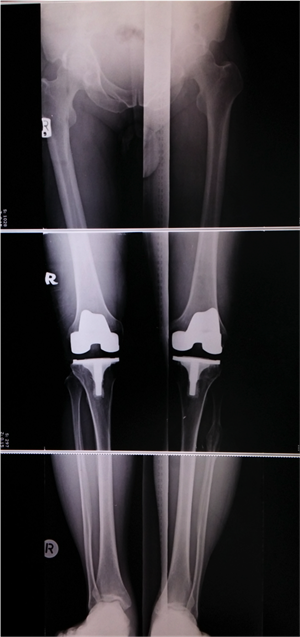

ในวันนี้ขอยกตัวอย่างผู้ป่วยโรคข้อเข่าเสื่อมทั้ง 2 ข้าง ที่ทำให้ผู้ป่วยมีอาการปวดข้อเข่า เดินลำบาก ข้อเข่าผิดรูป เดินเซและหกล้มได้ง่าย ซึ่งทำให้ผู้ป่วยใช้ชีวิตอย่างลำบากเป็นระยะเวลานานถึง 2 ปี ผู้ป่วยมีอาชีพรับราชการตำรวจ ทนทุกข์ทรมานจากอาการปวดเข่ามานาน ผู้ป่วยให้ประวัติว่า “เคยเจ็บเข่าจากอุบัติเหตุเล่นฟุตบอล จากนั้นก็เจ็บเข่าเป็นๆ หายๆ เรื่อยมา ในระยะสองปีมานี้อาการปวดเพิ่มขึ้นมากเรื่อยๆ คนรอบข้างเริ่มทัก โดยเฉพาะคุณแม่บอกว่าเดินไม่สวย เดินแปลกๆ เดินขาไม่ตรง เราก็ไม่ค่อยใส่ใจเท่าไหร่ จนมีอาการเจ็บมากจนทนไม่ไหว มาพบแพทย์ที่โรงพยาบาล แพทย์ได้ส่งตรวจทำการเอกซเรย์ เห็นได้ชัดเจนว่ากระดูกเข่าของเราชิดเข้าด้านในท่ายืนตรง แพทย์ได้แนะนำให้รักษาโดยการผ่าตัด ตอนแรกรู้สึกกังวล แต่เห็นกระดูกเข่าของตนเองจากภาพถ่ายรังสีแล้วก็คิดว่าถ้าปล่อยทิ้งไว้เข่าก็จะต้องชิดเข้ามากเรื่อยๆ ยังไงก็ต้องผ่าอยู่ดี และคิดว่าการเข้ารับการผ่าครั้งนี้ต้องเจ็บ ต้องปวดและใช้เวลาพักฟื้นนานแน่ๆ มีความกังวลว่ากระบวนการรักษาการผ่าตัดมันเป็นอย่างไร แพทย์จะทำอะไรกับเราบ้าง แต่หลังจากการได้คุยและได้รับคำแนะนำจากแพทย์ที่จะทำการผ่าตัด พร้อมกับเข้าไปศึกษาถึงวิธีการรักษา การปฏิบัติตัวและตัวอย่างประวัติการรักษาจากผู้ป่วยที่เคยรับการผ่าตัดรักษาเปลี่ยนข้อเข่าเทียมแล้ว ได้คลายความกังวลลงมาบ้าง หลังจากรับการรักษาด้วยการผ่าตัดเปลี่ยนข้อเข่าเทียมแล้วไม่ได้เจ็บปวดอย่างที่คิดไว้ สองวันแรกหลังผ่าตัดไม่ปวดเลย และเริ่มไปทำกายภาพ หัดเดินด้วยไม้สี่ขา หัดเหยียดเข่า งอเข่า ประมาณวันที่สี่เริ่มมีอาการระบม ปวด แพทย์ได้ให้ยาแก้ปวด อาการปวดทุเลาลงไป ทำกายภาพต่อได้สบาย มาตอนนี้หลังผ่าตัดประมาณยี่สิบวัน รู้สึกดีมาก แผลแห้งดี งอเหยียดเข่าได้เต็มที่ ยืนขาตรง เดินตรง เหมือนกับได้ชีวิตใหม่ขึ้นมาอีกครั้ง” สำหรับผู้ป่วยรายนี้ เนื่องจากเข่าของผู้ป่วยมีอาการผิดรูปทั้ง 2 ข้าง ทำให้ไม่สามารถเดินได้เป็นปกติ หลังจากที่ได้พูดคุยและอธิบายถึงข้อดีและความเสี่ยงจากการผ่าตัด เช่น โอกาสของการติดเชื้อ การเกิดลิ่มเลือดอุดกั้นในเส้นเลือดดำ การควบคุมอาการปวดหลังการผ่าตัด ก็ได้พิจารณารักษาด้วยการผ่าตัดเปลี่ยนข้อเข่าเทียมพร้อมกันทั้ง 2 ข้างให้กับผู้ป่วย หลังการผ่าตัดได้มีการให้ยาระงับปวดด้วยการวางสายเพื่อให้ยาลดอาการปวดที่โพรงประสาทในส่วนกระดูกสันหลัง ซึ่งผลการผ่าตัดทุกอย่างเป็นไปตามเป้าหมายที่วางไว้ คือ ลดอาการปวดข้อเข่าให้กับผู้ป่วย แก้ไขความผิดรูปของข้อเข่าทั้ง 2 ข้าง ทำให้ผู้ป่วยสามารถกลับมาเดินได้อย่างปกติ ทำให้ผู้ป่วยสามารถกลับไปใช้ชีวิตในสังคมได้อย่างมีความสุข ทำให้คุณภาพชีวิตของผู้ป่วยดีขึ้นเป็นอย่างมาก

สำหรับการปฏิบัติตนหลังการผ่าตัดเปลี่ยนข้อเข่าเทียม ได้แก่ การทำกายภาพบำบัด เพื่อให้ข้อเข่าสามารถเหยียดได้ตรง และงอข้อเข่าได้เพิ่มมากขึ้น การฝึกเดิน และการควบคุมอาการปวดหลังผ่าตัด ซึ่งส่วนใหญ่ยังอาจมีความจำเป็นที่ต้องได้รับยาแก้ปวดหลังการผ่าตัดประมาณ 1 – 3 เดือนแรกหลังการผ่าตัด หลังจากนั้นก็ไม่จำเป็นต้องรับประทานยาแก้ปวด สามารถขับรถได้หลังการผ่าตัด เมื่อผู้ป่วยสามารถควบคุมการทำงานของข้อเข่าได้ดี และไม่มีอาการปวดข้อเข่าแล้ว ซึ่งส่วนใหญ่ก็ประมาณ 3 เดือนหลังการผ่าตัด ในกรณีที่ผู้ป่วยจำเป็นต้องไปทำหัตถการเกี่ยวกับทันตกรรม ผู้ป่วยจำเป็นต้องปรึกษาแพทย์ผู้ทำการผ่าตัดเพื่อที่จะรับยาปฏิชีวนะ เพื่อป้องกันการติดเชื้อจากการทำหัตถการที่ฟันมายังที่บริเวณข้อเข่าข้างที่ผ่าตัดเปลี่ยนข้อเข่าเทียม